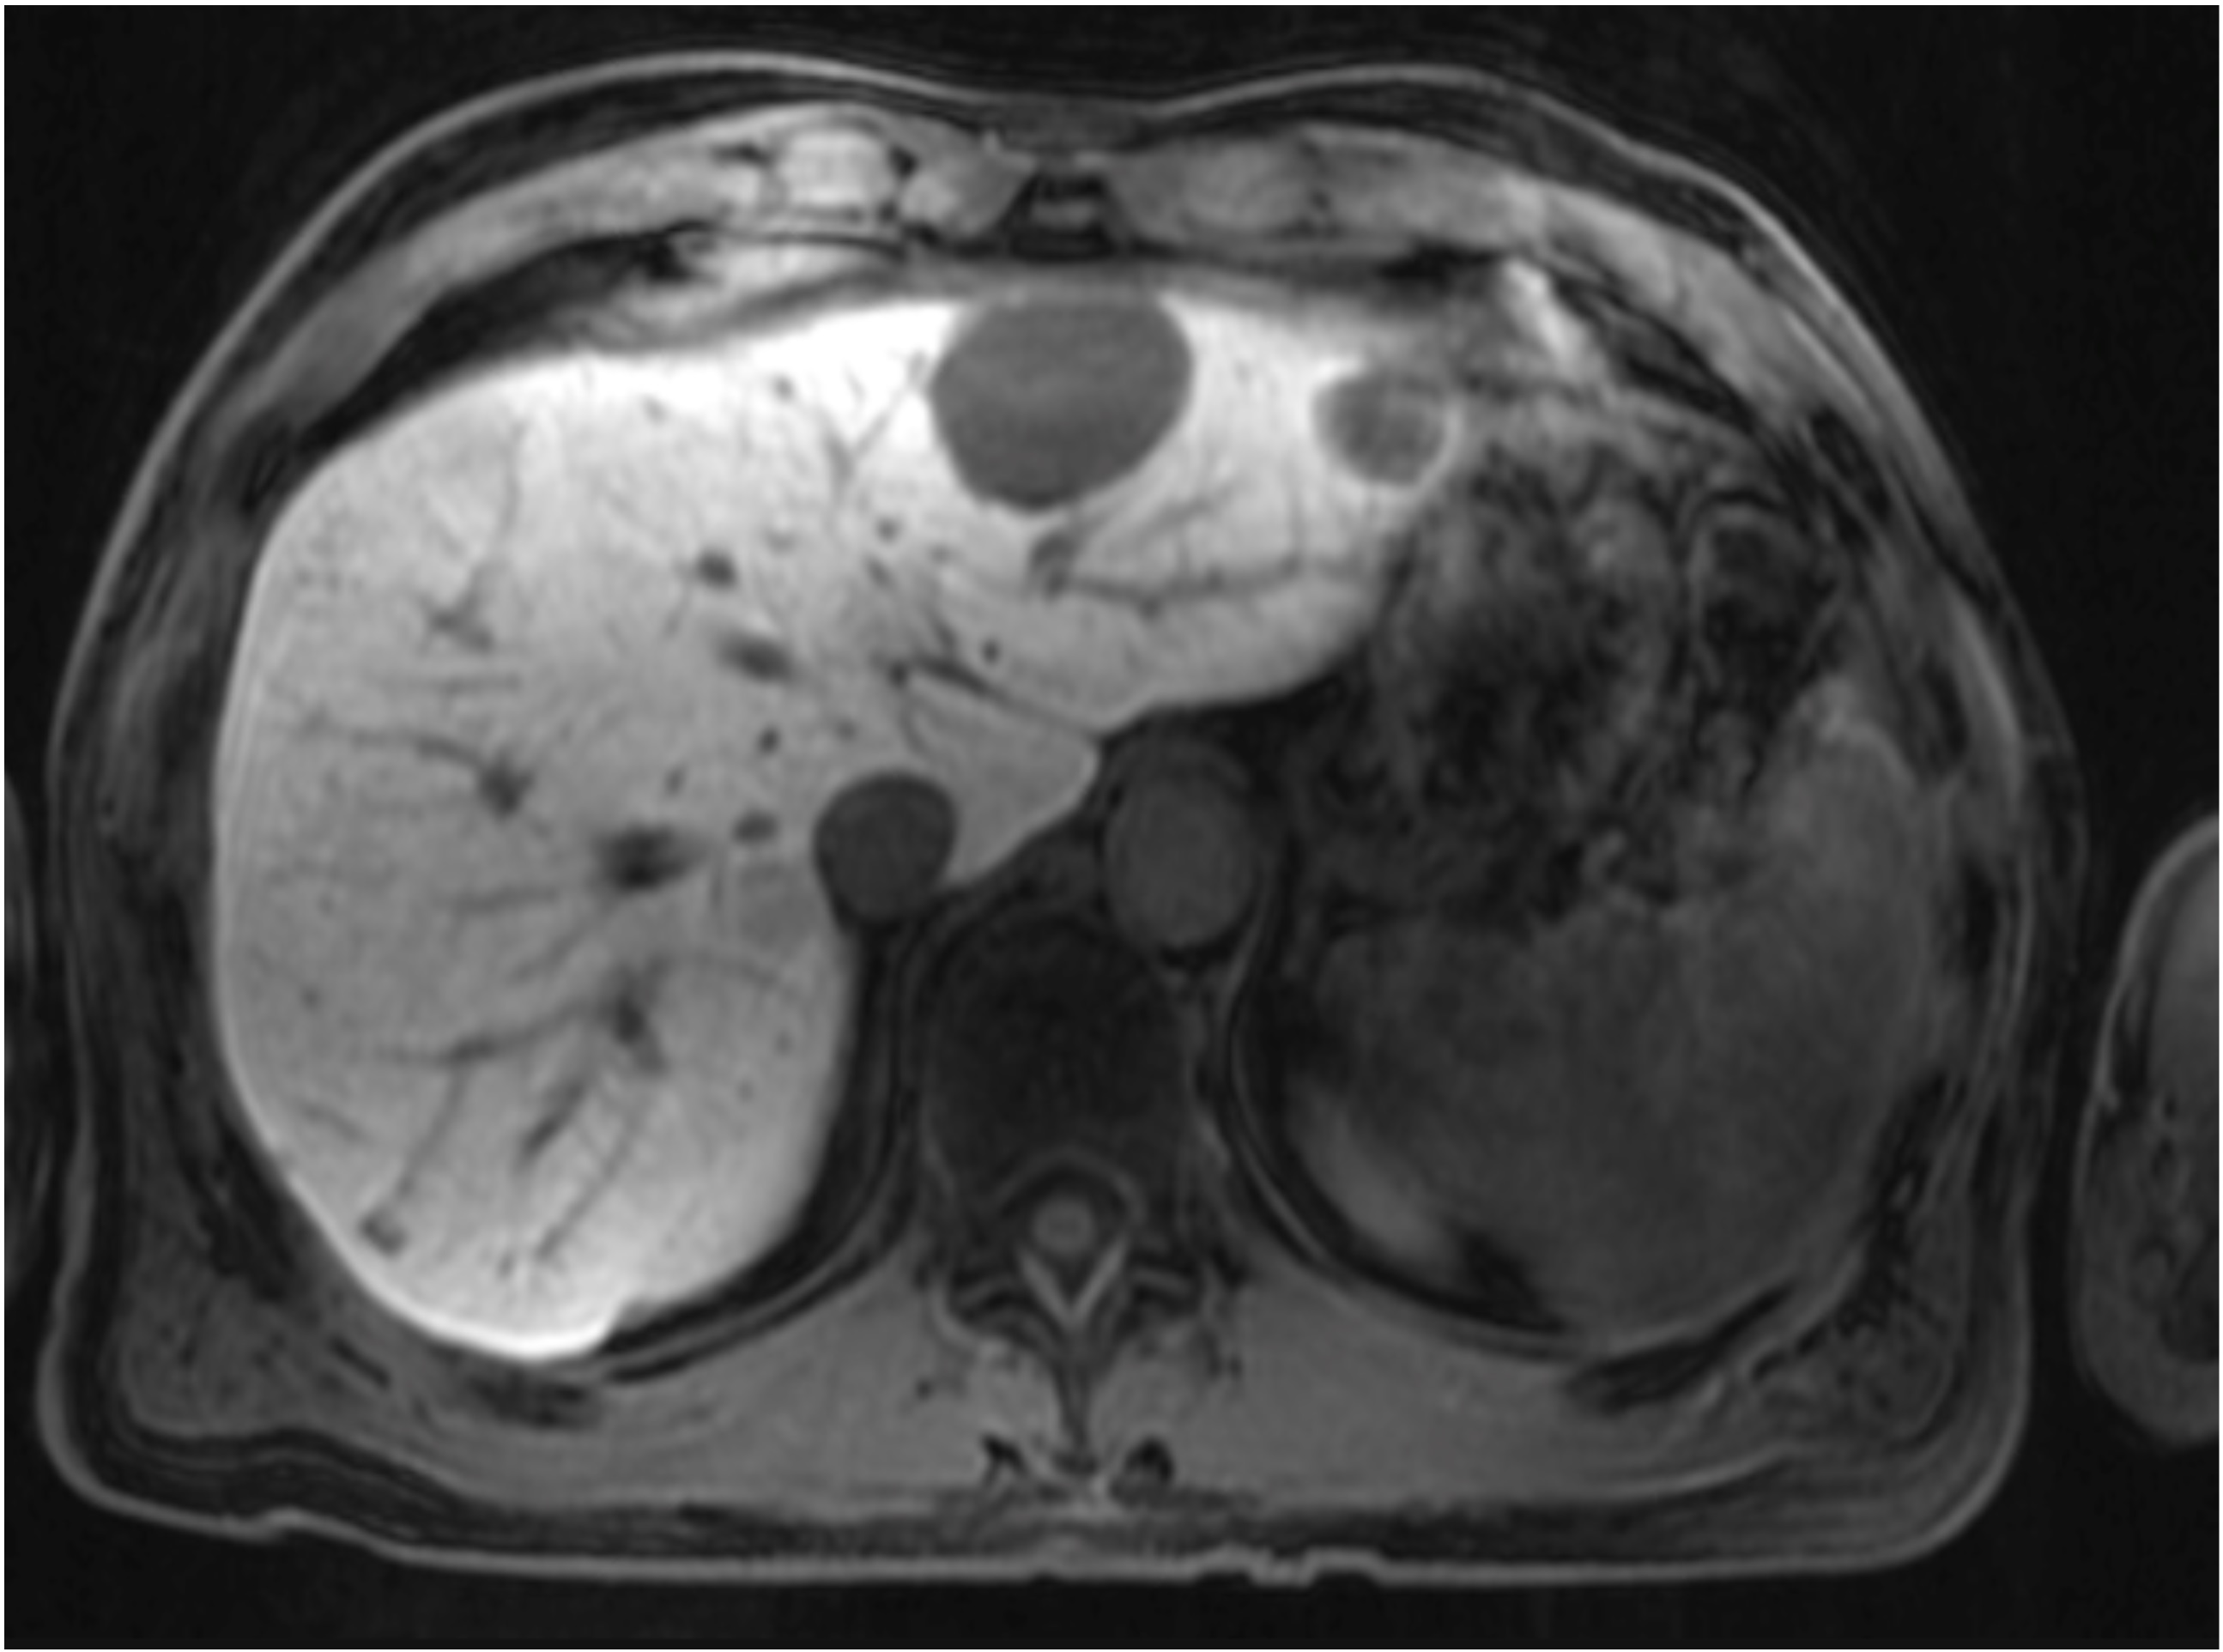

Three FDG PET MRI images of various views plus a liver MRI image with hepatobiliary specific contrast used to detect liver metastasis from colon cancer.

FDG PET/MRI with hepatobiliary specific contrast agent used to detect liver metastasis from colon cancer.